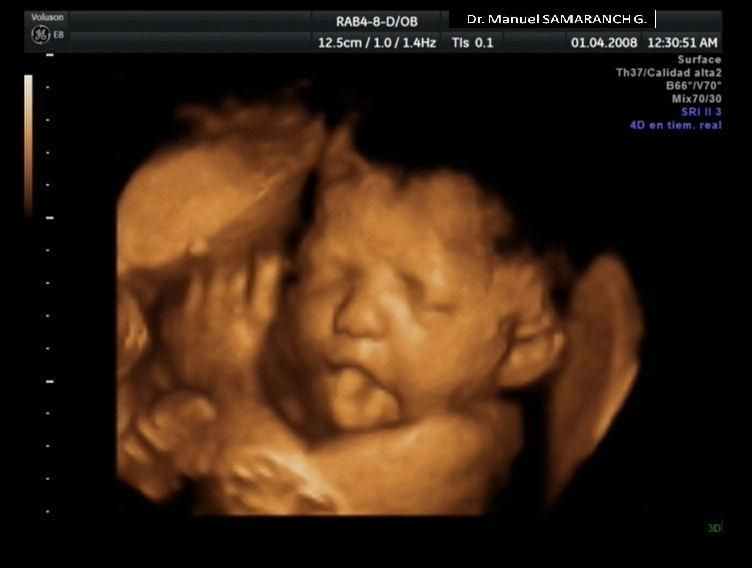

Fotos y vídeos